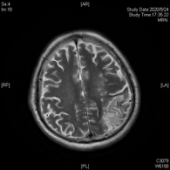

患者老李由于突发脑梗死,一觉醒来竟然听不懂别人的一句话,也说不出一个字,就连简单的“a”、“o”、“e”都说不出来。这对于作为教师的老李来说,无疑是晴天霹雳,当头一棒。经头颅核磁检查显示:老李的左侧大脑大面积脑梗死。老李是右利手,他的优势半球为大脑左半球,也就是支配我们语言的脑区。然而,不幸地是这个区域脑区几乎没有一丁点地儿在这场灾难中幸存,自发语极少,听觉理解、文字理解严重障碍,命名、复数、读词不能,听、说、读、写所有语言模式受到严重损害,诊断为完全性失语伴有言语失用。于是在他人的眼里,他似乎变得“又聋又哑”,既听不明白别人说什么也说不出来一句话,像是他的世界屏蔽了信号,接收不到任何语言的输入,也输出不了任何语言符号。这可急坏了老李的老伴,这以后可怎么办呀?